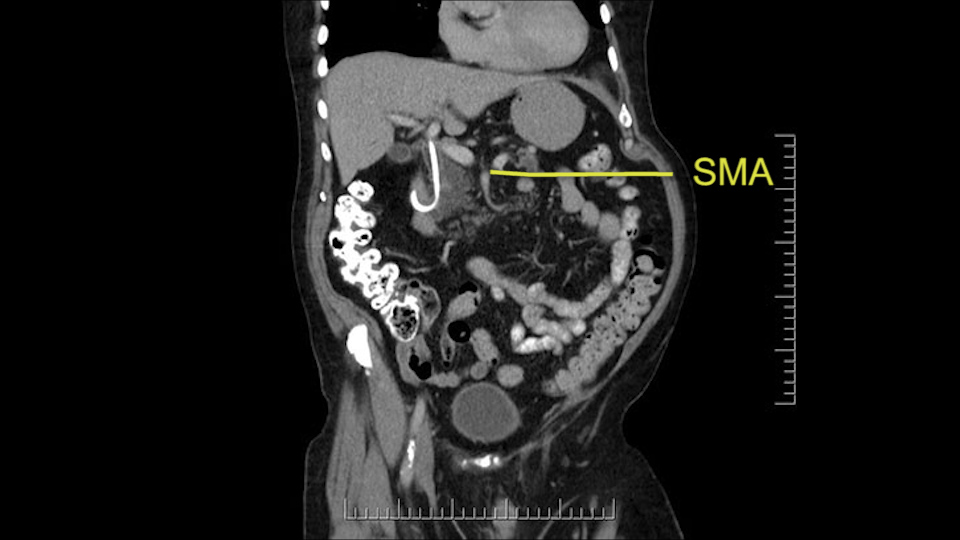

The other thing I look at is the gastroepeiploic arcade- which is this thing here- which is where the gastroepeiploic vein joins the portal vein. I call it the gateway to the neck of the pancreas because you pretty much have to divide it to get to the neck. The middle colic vein usually drains either into it or nearby. I think we’re seeing it here. Again,that can be divided and I usually divide those two and it helps me get under the neck. Again, there’s no issues here with the tumor so it’s nice from that perspective. If I was concerned about the vein, which I’m not here, I would go to the coronal view. It’s a nice way to look at the vein on just a couple of cuts and you can see a beautiful view of it here. There’s the portal vein, there’s the head of the pancreas. There’s the tumor. It’s a little closer here than it looks on the other one. I doubt it’s involved. If it’s touching, it may not be invading it but even if it was, it's a short segment. Anyways, there’s the SMV there’s the splenic vein, and everything looks good. You can see the stent. I ignore the stent. It’s the most dramatic looking thing in the picture but it’s actually the least important.

Then either through the coronal or the axial, I’ll do both. Look at the SMA -which is here- I had already looked at it and I don’t see any involvement. There’s the SMA with a nice fat plane between the SMA and the tumor. Over here you can see on the axial, there’s the SMA. Everything on the right side of the SMA has got some nice black around it, which is fat, which means probably no tumor [no tumor, no tumor]. Follow it up to the origin, coming off the aorta. So those are the two technical things that I worry about: the SMA and the SMV.